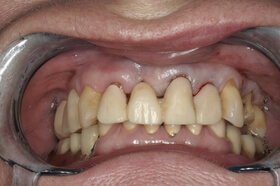

Több, mint tízéves hidak, elkopott fogak. Kezelési terv: a régi hidak cseréje és a többi fog ellátása fém-kerámia koronákkal

Az elkészült fém-kerámia koronák, hidak